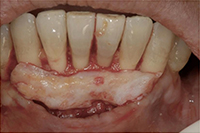

歯の根が露出して部分の歯ぐきが再生。